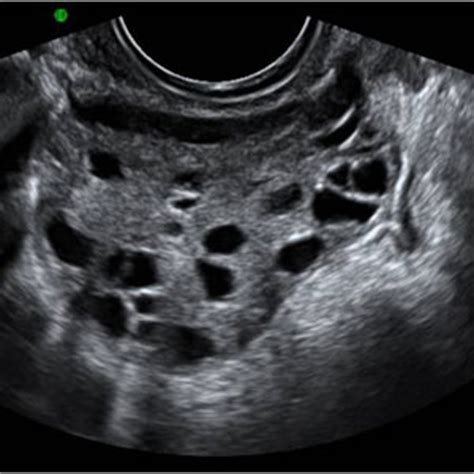

Polycystic ovarian syndrome causes cysts, (also not cancerous), that suddenly occur in one or both ovaries. It is why further medical testing is performed, so that they can distinguish just what is. However, this risk could be because of possible cysts on the ovaries that may occur in some women with pcos. Ovarian cysts are a common occurrence among women of reproductive age. 1 irregular periods, or a lack of periods, can cause the endometrium to build up and become thick. By understanding a patient's family history and lifestyle, the nurse can encourage patients to take action that supports their health and. Why women with this disease may have a higher exposure or higher infection rate is not known. 14 year old with large ovarian cyst.

So is there a connection between fibroids and polycystic ovarian syndrome (pcos)? Researches have shown that women with pcos have a high risk of ovarian cancer; Around 90% of ovarian cancers occur in women. However, most early ovarian tumors. If low levels of healthy bacteria can cause ovarian cancer, then it could rightly be inferred that bad vaginal hygiene habits may play a part in heightening the risk of ovarian cancer. Women with pcos may be at higher risk for type 2 diabetes, high blood pressure, heart problems, and endometrial cancer. Pcos can cause missed or irregular menstrual periods, excess hair growth, acne, infertility, and weight gain. A pelvic exam, when your ovaries and uterus are checked for size, shape and consistency, can sometimes detect some reproductive system cancers at an early stage. There's no cure, but a healthy lifestyle and hormonal therapies can mitigate symptoms. There are several types of ovarian cysts. However, this risk could be because of possible cysts on the ovaries that may occur in some women with pcos. Other ovarian cyst symptoms may include pelvic pain, high blood pressure, lower back pain, abdominal pressure and nausea. Other women have mistaken their swollen abdomen for being pregnant.

Pcos can cause missed or irregular menstrual periods, excess hair growth, acne, infertility, and weight gain. Ovarian cysts of less than 1 centimeter (0.4 inches) in size are common in postmenopausal women, the vast majority of which will be benign. It is why further medical testing is performed, so that they can distinguish just what is. Patients with polycystic ovarian syndrome often have painful periods, dr. This is a common phenomenon in late postmenopausal women, which can trigger swelling of the ovaries along with the formation of ovarian cysts.

14 year old with large ovarian cyst. Only 22% for other women. There's no clear link between ovarian cancer and pcos. However, this risk could be because of possible cysts on the ovaries that may occur in some women with pcos. Ovarian cysts are a common occurrence among women of reproductive age. Learn about the connection between a missed period and ovarian cancer. This is a common phenomenon in late postmenopausal women, which can trigger swelling of the ovaries along with the formation of ovarian cysts. For example, heavy menstrual bleeding could be caused by a range of conditions, such as uterine fibroids, polyps, bleeding disorders, certain medications, or pelvic inflammatory disease, in addition to pcos.

To read more about pcos, click here. There's no clear link between ovarian cancer and pcos. This test can be useful as a tumor marker to help guide treatment in women known to have ovarian cancer, because a high level often goes down if treatment is working. However, ovarian cancer is usually not diagnosed until after it has spread and is difficult to cure. However, most early ovarian tumors. Ovarian cysts of less than 1 centimeter (0.4 inches) in size are common in postmenopausal women, the vast majority of which will be benign. Pcos can cause missed or irregular menstrual periods, excess hair growth, acne, infertility, and weight gain. Ovarian cancer and cysts have similar symptoms and signs, for example, pain during intercourse, pelvic pain, and urinary problems. Around 90% of ovarian cancers occur in women. Why women with this disease may have a higher exposure or higher infection rate is not known. Ovarian cysts with all of the features of ovarian cancer warrant the recommendation of removal of the cyst to definitively determine if it is benign or malignant. So basically i don't think that ovarian cancer could be mistaken for polycystic ovaries at this moment but on the other hand patients diagnosed with polycystic ovary syndrome are at risk of getting diabetes, hypertension and increased levels of triglyceride and cholesterol which could cause cardiovascular diseases. In fact, half of women with pcos get pregnant without any medical intervention.

Stay informed, educate patients, be alert for risk factors, encourage screening, and treat them with compassionate care. In fact, half of women with pcos get pregnant without any medical intervention. The onset of polycystic ovarian syndrome can bring about conditions that are also central to an environment that encourages the creation of cancer. There's no cure, but a healthy lifestyle and hormonal therapies can mitigate symptoms. It is commonly thought that ovarian cancer has few if any symptoms prior to reaching and advanced stage. Ovarian cysts are common among women of all ages. Ovarian cancer and cysts have similar symptoms and signs, for example, pain during intercourse, pelvic pain, and urinary problems. There's no clear link between ovarian cancer and pcos. There are several types of ovarian cysts. Likewise, while some research indicates a possible relationship between pcos and ovarian cancer, the human reproduction update suggests that you're no more likely to develop ovarian cancer than someone without pcos. The three women featured below were all diagnosed in their teens and 20s and had the characteristic. This test can be useful as a tumor marker to help guide treatment in women known to have ovarian cancer, because a high level often goes down if treatment is working. Pcos can be difficult to diagnose because some of its symptoms have a variety of potential causes.